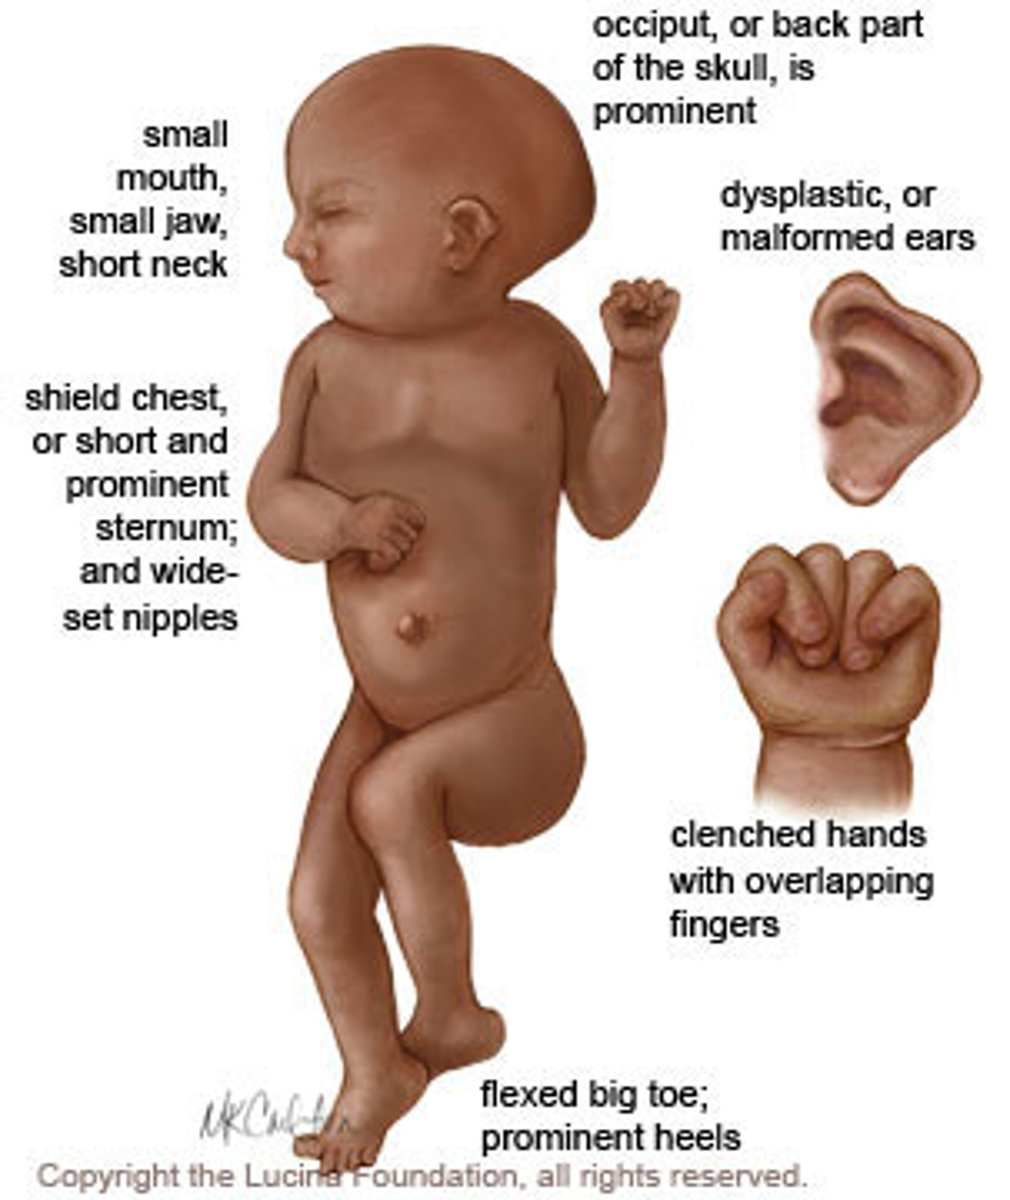

Infant with microcephaly, rocker-bottom feet, clenched hands, and structural heart defect

Edwards Syndrome (trisomy 18)

Mnemonic: E=election age at 18